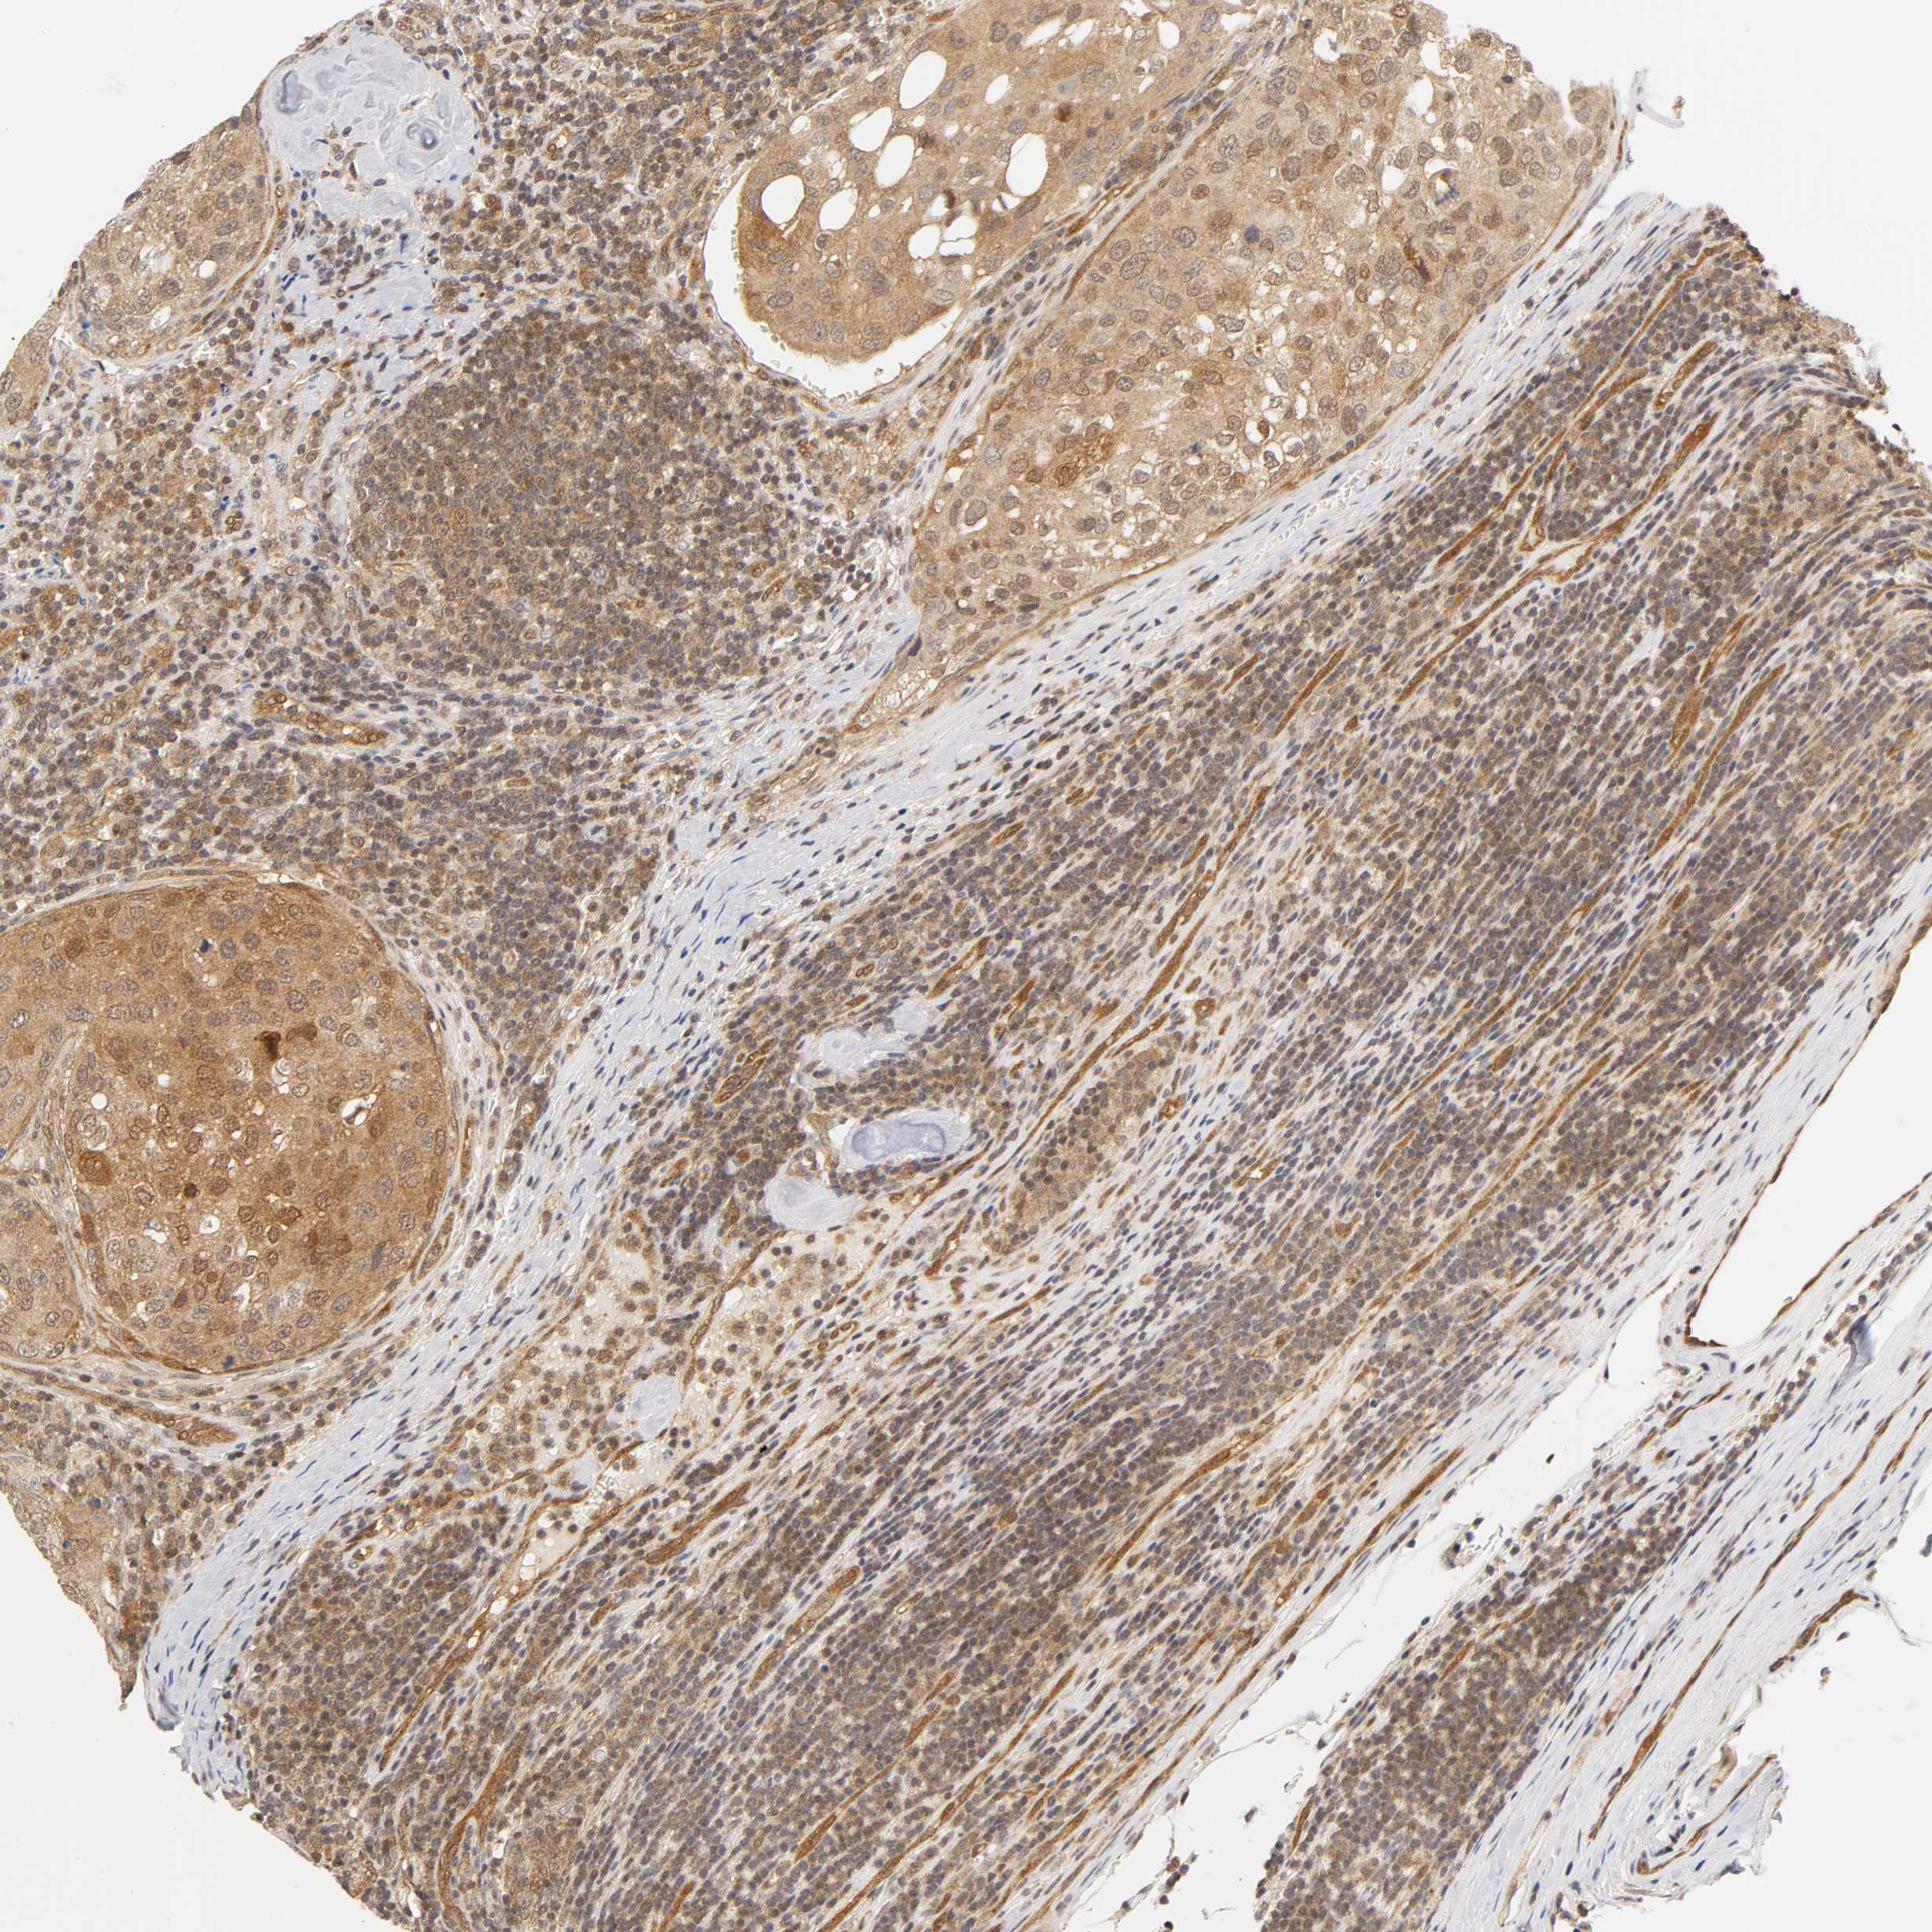

UROTHELIAL CANCER - Protein expressioni

A mouse-over function shows sample information and annotation data. Click on an image to view it in a full screen mode. Samples can be filtered based on level of antibody staining by selecting one or several of the following categories: high, medium, low and not detected. The assay and annotation is described here.

Note that samples used for immunohistochemistry by the Human Protein Atlas do not correspond to samples in the TCGA dataset.

Antibody stainingi

Antibody staining in the annotated cell types in the current human tissue is reported as not detected, low, medium, or high, based on conventional immunohistochemistry profiling in selected tissues. This score is based on the combination of the staining intensity and fraction of stained cells.

Each image is clickable and will lead to virtual microscopy that enables deeper exploration of all samples and also displays staining intensity scores, fraction scores and subcellular localization as well as patient and tissue information for each sample.

Antibody HPA003928

Antibody CAB004214

Urothelial carcinoma, High grade

Urothelial carcinoma, Low grade